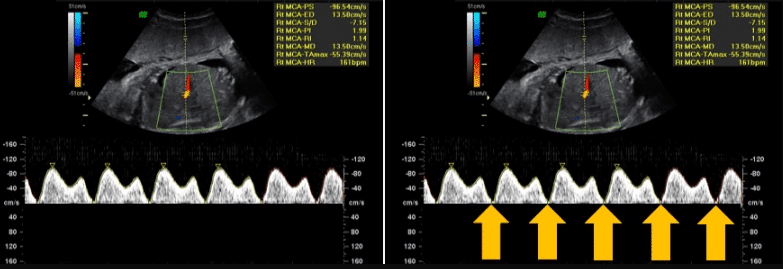

Artéria cerebral média (ACM)

Utiliza-se o Doppler da artéria cerebral média para avaliar a resposta fetal à hipóxia crônica causada por insuficiência placentária. Nessa condição, ocorre uma redistribuição do fluxo sanguíneo para órgãos vitais, como cérebro, coração e glândulas adrenais, fenômeno conhecido como centralização fetal.

Portanto, no Doppler, observa-se aumento do fluxo diastólico e redução da resistência na artéria cerebral média, sendo considerados alterados os valores de IP abaixo do percentil 5 para a idade gestacional.